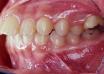

case dot 扶正大臼齒